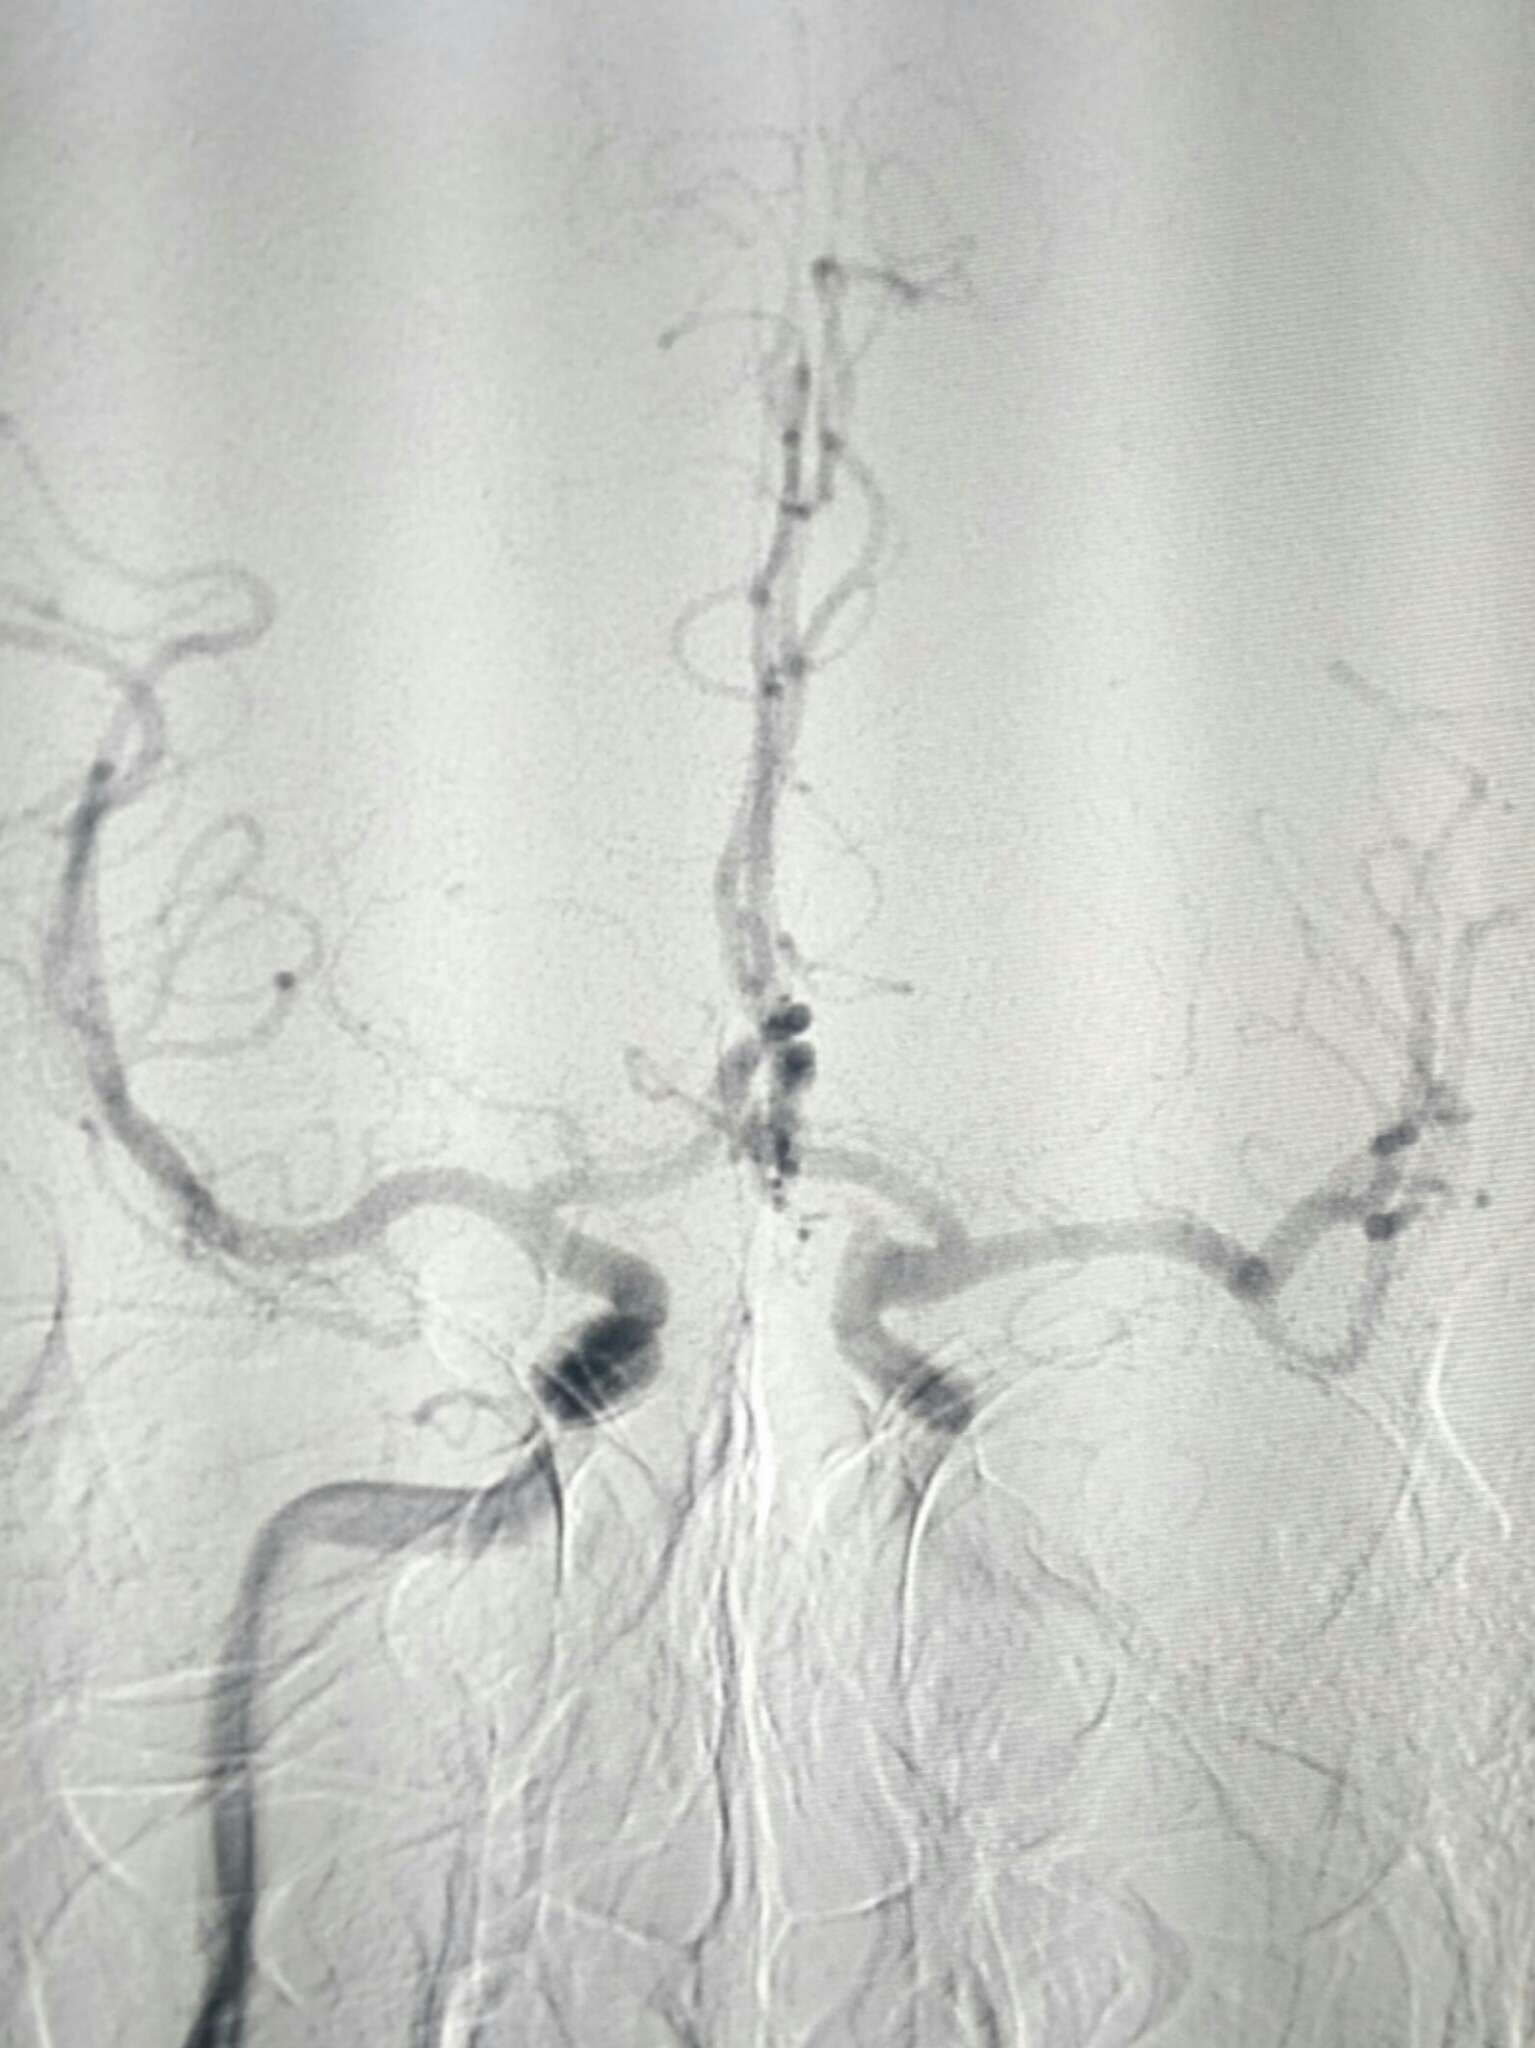

正位像栓塞影像满意

侧位像满意